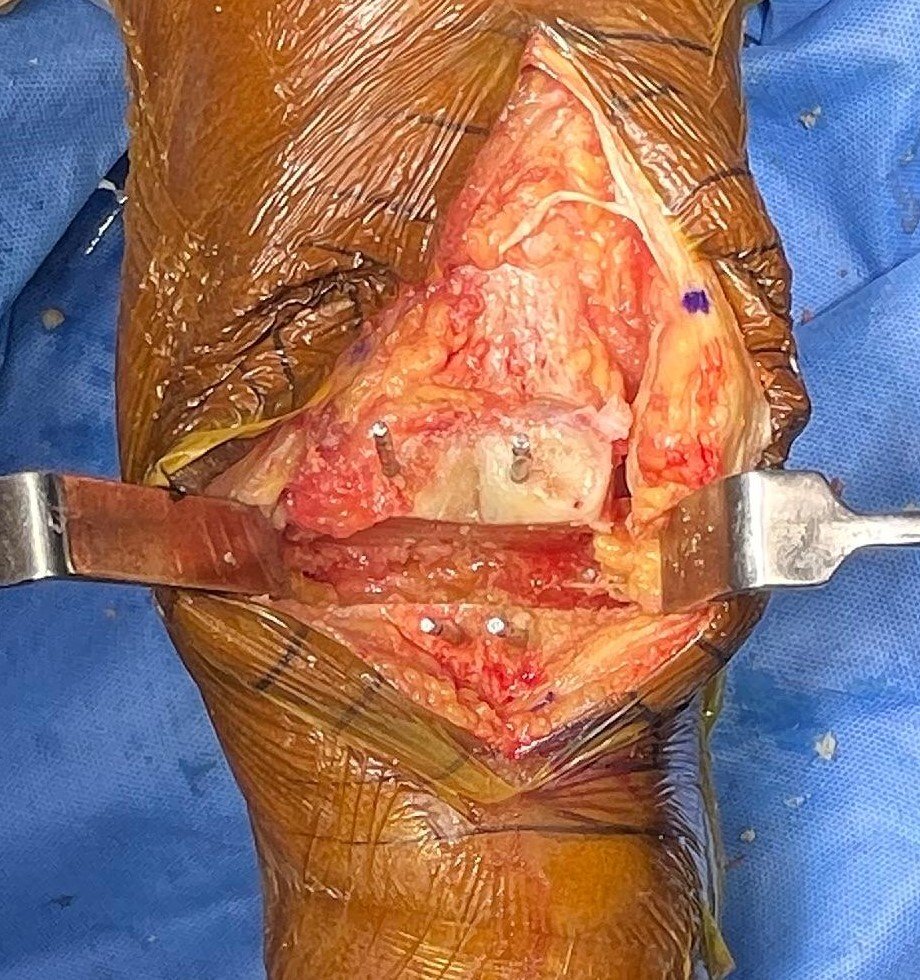

Synovitis with Loose Body in Rheumatoid Arthritis

Intra-Op (Photos)